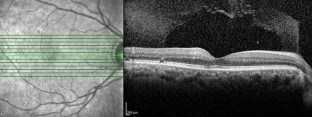

Fig. 1

Fig. 2

Fig. 3

Fig. 4

Fig. 5